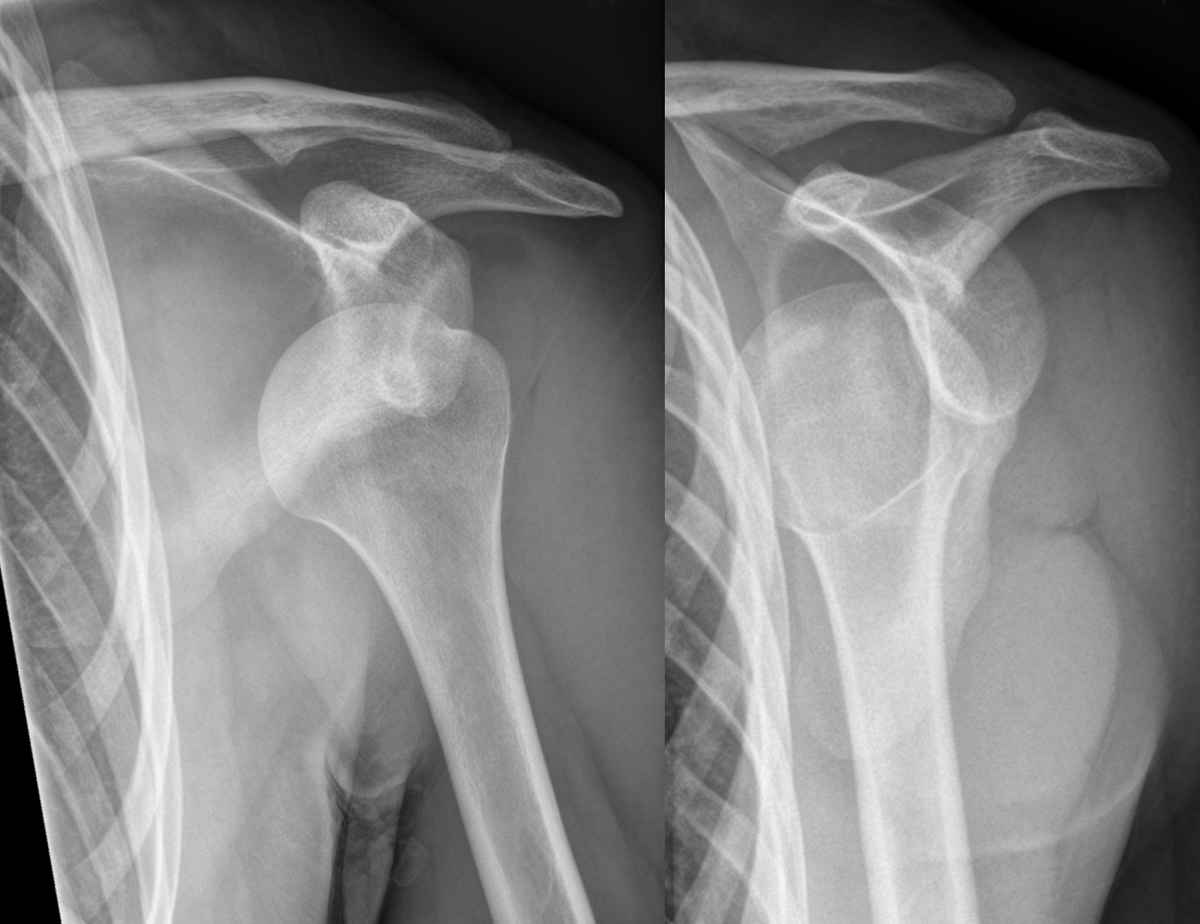

What investigation should be done for a shoulder dislocation?

Plain XR (AP + lat)

What will a AP view plain XR show in an ANTERIOR shoulder dislocation?

- Humeral head visibly out of glenoid fossa (CAN see greater tubercle)

- Humeral head overlaps w other bony structures (aka no GAP)

What will a AP view plain XR show in a POSTERIOR shoulder dislocation? (2 things)

- “Light bulb sign” = humerus fixed in internal rotation (aka CAN’T see greater tubercle)

- Gap between humerus and glenoid (no overlapping)

What is a Lat view plain XR used for in a shoulder dislocation?

To differentiate between ANT + POST dislocations